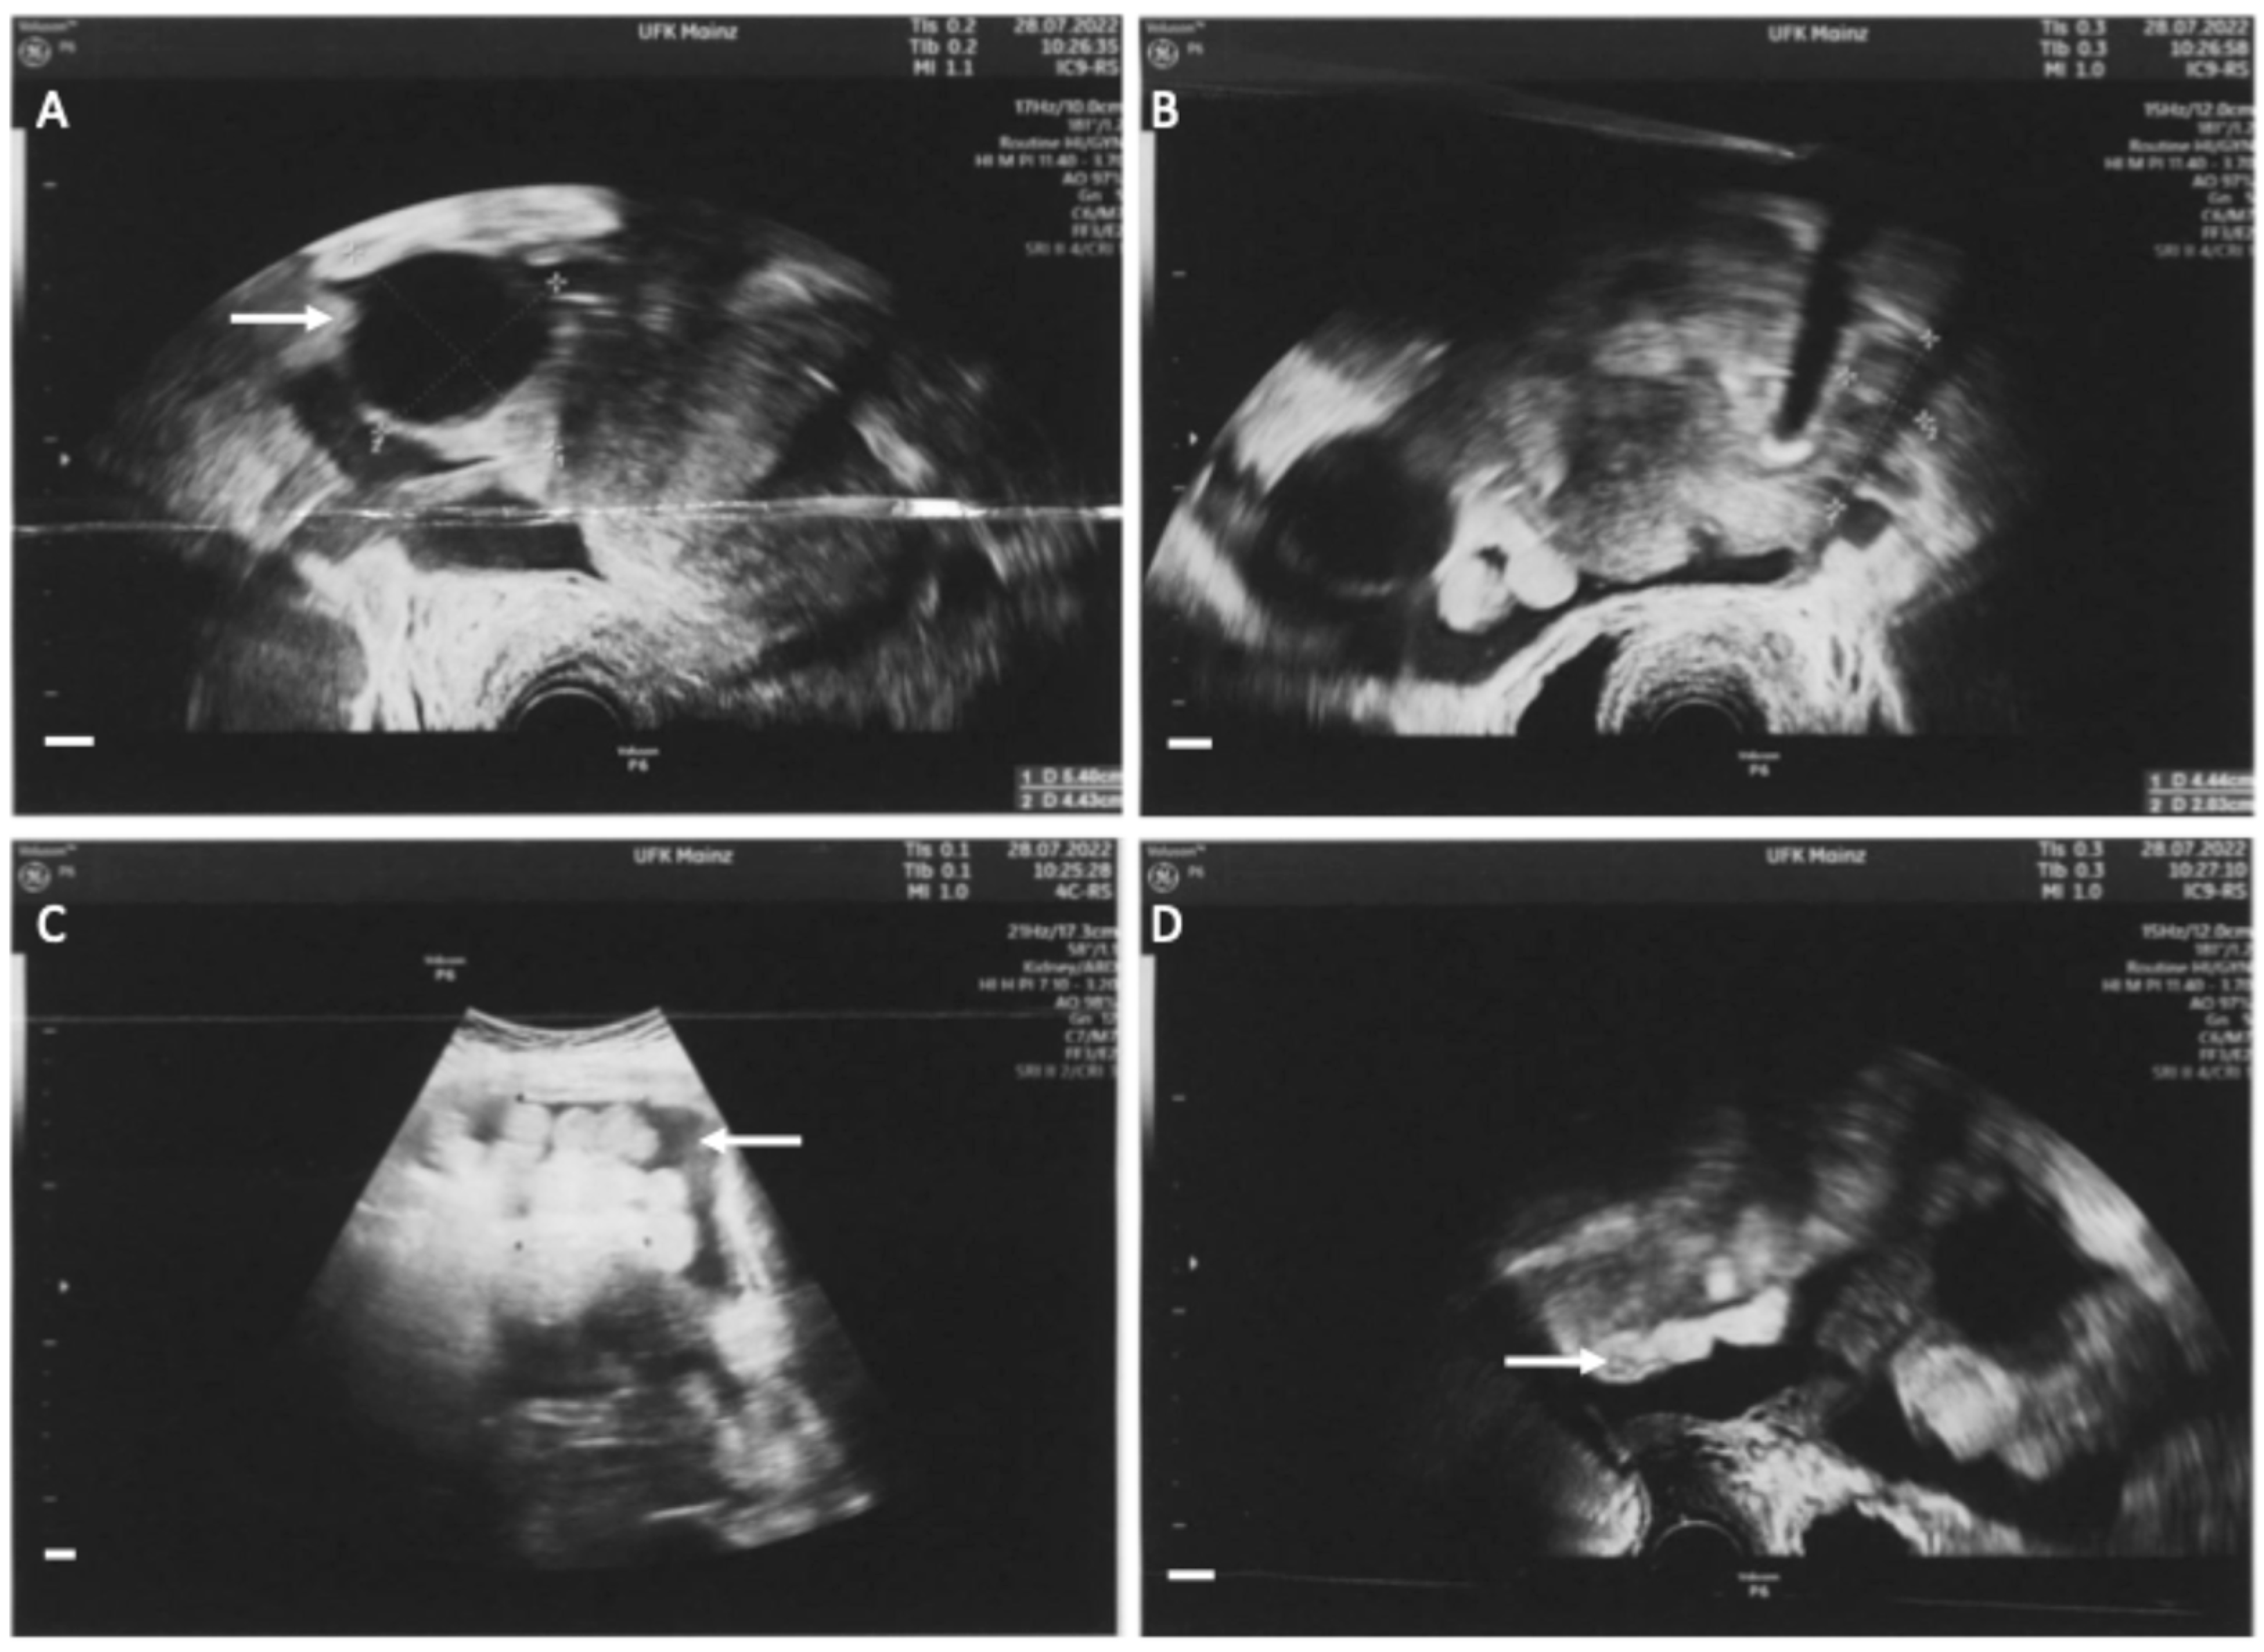

Figure 3.

Intraoperative images of staging laparoscopy. A laparoscopy was performed to confirm diagnosis after biopsy. Biopsies were taken from the diaphragm, the liver around the falciform ligament and from the right fimbrial funnel. All biopsies revealed the diagnosis of a B-cell lymphoma. The German guideline on ovarian cancer does not recommend laparoscopy [4], however the American guideline NCCN states that laparoscopy may be appropriate to obtain biopsy material and to confirm the diagnosis [5]. (A): White-yellow marbling of the liver (white arrow) and white milky ascites (black arrow). (B): White stipple bedding on the diaphragm (white arrow). (C): Overview of the pelvis. Uterus without pathological findings; the fallopian tubes are enlarged (white arrow), paraovarian-cyst (black arrow). (D): Focused image of the right enlarged fallopian tube (white arrow) and the paraovarian-cyst of the right ovary (black arrow).